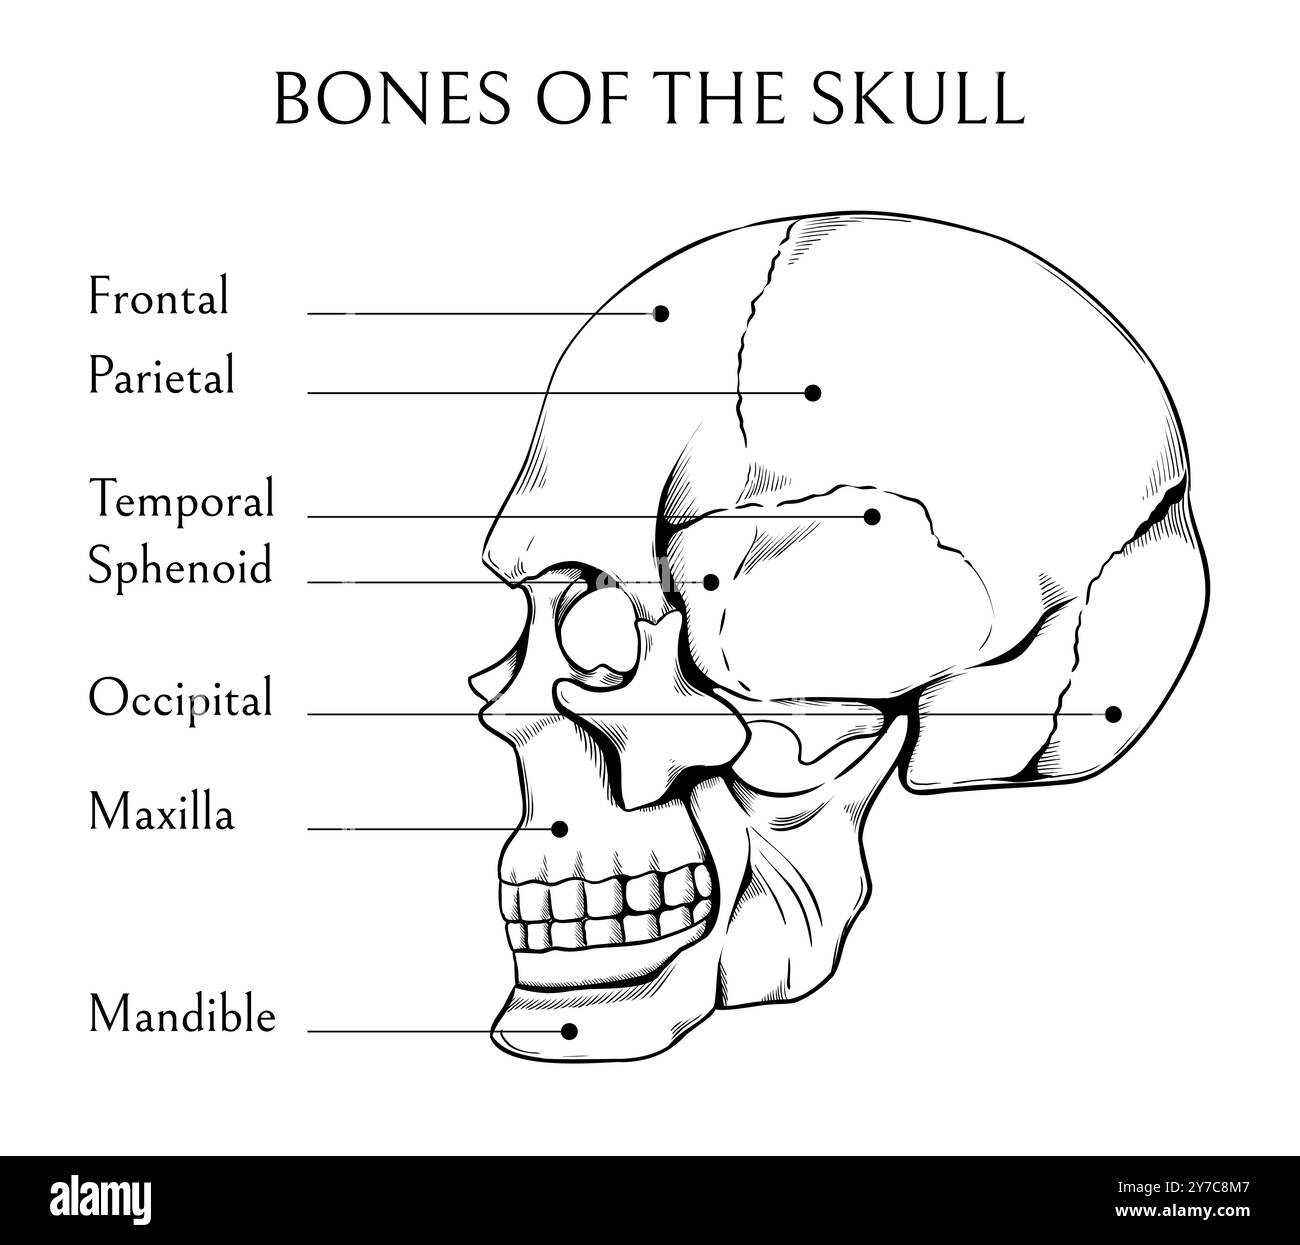

Schéma étiqueté des os du crâne humain - illustration de la vue anatomique latérale Illustration de Vecteurhttps://www.alamyimages.fr/image-license-details/?v=1https://www.alamyimages.fr/schema-etiquete-des-os-du-crane-humain-illustration-de-la-vue-anatomique-laterale-image614045686.html

Schéma étiqueté des os du crâne humain - illustration de la vue anatomique latérale Illustration de Vecteurhttps://www.alamyimages.fr/image-license-details/?v=1https://www.alamyimages.fr/schema-etiquete-des-os-du-crane-humain-illustration-de-la-vue-anatomique-laterale-image614045686.htmlRF2XK05F2–Schéma étiqueté des os du crâne humain - illustration de la vue anatomique latérale

OS faciaux dessinés à la main. Esquisse du crâne humain. Bannière éducative médicale. Diagramme de gravure de squelette. Encyclopédie des sciences médicales. Structure squelettique crânienne. Texte de l'inscription. Affiche d'anatomie vectorielle Illustration de Vecteurhttps://www.alamyimages.fr/image-license-details/?v=1https://www.alamyimages.fr/os-faciaux-dessines-a-la-main-esquisse-du-crane-humain-banniere-educative-medicale-diagramme-de-gravure-de-squelette-encyclopedie-des-sciences-medicales-structure-squelettique-cranienne-texte-de-l-inscription-affiche-d-anatomie-vectorielle-image623279239.html

OS faciaux dessinés à la main. Esquisse du crâne humain. Bannière éducative médicale. Diagramme de gravure de squelette. Encyclopédie des sciences médicales. Structure squelettique crânienne. Texte de l'inscription. Affiche d'anatomie vectorielle Illustration de Vecteurhttps://www.alamyimages.fr/image-license-details/?v=1https://www.alamyimages.fr/os-faciaux-dessines-a-la-main-esquisse-du-crane-humain-banniere-educative-medicale-diagramme-de-gravure-de-squelette-encyclopedie-des-sciences-medicales-structure-squelettique-cranienne-texte-de-l-inscription-affiche-d-anatomie-vectorielle-image623279239.htmlRF2Y60R0R–OS faciaux dessinés à la main. Esquisse du crâne humain. Bannière éducative médicale. Diagramme de gravure de squelette. Encyclopédie des sciences médicales. Structure squelettique crânienne. Texte de l'inscription. Affiche d'anatomie vectorielle

OS faciaux dessinés à la main. Esquisse du crâne humain. Bannière éducative médicale. Diagramme de gravure de squelette. Encyclopédie des sciences médicales. Structure squelettique crânienne. Texte de l'inscription. Affiche d'anatomie vectorielle Illustration de Vecteurhttps://www.alamyimages.fr/image-license-details/?v=1https://www.alamyimages.fr/os-faciaux-dessines-a-la-main-esquisse-du-crane-humain-banniere-educative-medicale-diagramme-de-gravure-de-squelette-encyclopedie-des-sciences-medicales-structure-squelettique-cranienne-texte-de-l-inscription-affiche-d-anatomie-vectorielle-image624146103.html

OS faciaux dessinés à la main. Esquisse du crâne humain. Bannière éducative médicale. Diagramme de gravure de squelette. Encyclopédie des sciences médicales. Structure squelettique crânienne. Texte de l'inscription. Affiche d'anatomie vectorielle Illustration de Vecteurhttps://www.alamyimages.fr/image-license-details/?v=1https://www.alamyimages.fr/os-faciaux-dessines-a-la-main-esquisse-du-crane-humain-banniere-educative-medicale-diagramme-de-gravure-de-squelette-encyclopedie-des-sciences-medicales-structure-squelettique-cranienne-texte-de-l-inscription-affiche-d-anatomie-vectorielle-image624146103.htmlRF2Y7C8M7–OS faciaux dessinés à la main. Esquisse du crâne humain. Bannière éducative médicale. Diagramme de gravure de squelette. Encyclopédie des sciences médicales. Structure squelettique crânienne. Texte de l'inscription. Affiche d'anatomie vectorielle